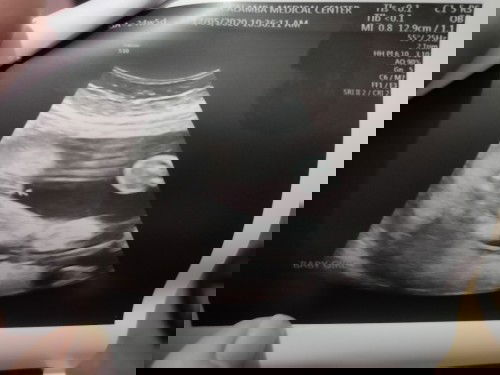

Sure na po kayang baby girl to pag ganito itsura? 😁 Nung isang araw lang po yan, 24w 5d ako nagpaCongenital Anomaly Scan. 😊 Nabother lang ako bigla nung may nabasa ako sa comment ng isang post na baby girl daw ang result nung 23rd week then nung ika-30th week inulit ang ultrasound tapos bigla nakitaan ng lawit. 😂 Hahaha! #firstbaby #pregnancy #1stimemom #joyofpregnancy